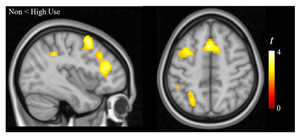

“En el análisis de las imágenes de resonancia magnética del cerebro de un subgrupo de niños del estudio, se observó que el uso de los videojuegos estaba asociado a un mejor funcionamiento de circuitos cerebrales que son importantes para la adquisición de nuevas habilidades a través de la práctica, concretamente de las conexiones entre los ganglios basales y los lóbulos frontales.” explica el Dr. Pujol.

Imágenes de resonancia magnética de las conexiones funcionales entre los ganglios basales y los lóbulos frontales (parte superior izquierda), conexiones muy importantes en la adquisición de nuevas habilidades a través de la práctica. El uso de los videojuegos está asociado a un mejor funcionamiento de estas conexiones, tal y como muestra el gráfico (parte superior derecha) y la comparación entre niños que no jugaban y los que jugaban más (parte inferior).